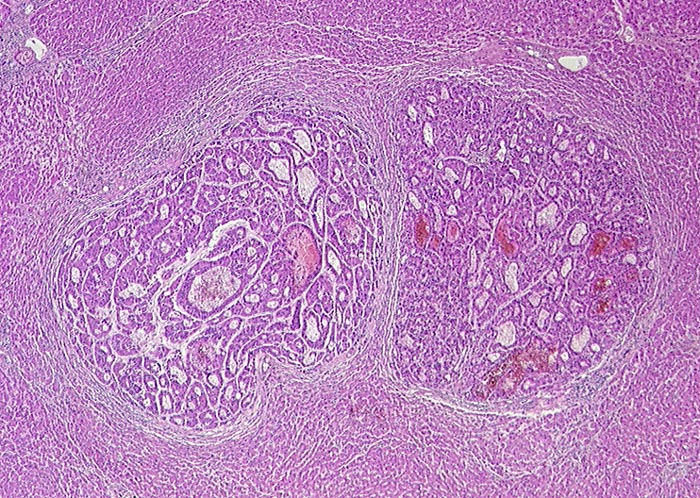

PathoPic – image database / PathoPic ID 1199 - Hepatozelluläres Karzinom

Hepatozelluläres Karzinom

Das Tumorgewebe in der Bildmitte ist diskret basophiler als das umgebende Leberparenchym. Leberzellähnliches Gewebe aus doppel- oder mehrreihigen Zellplatten. Diese bilden pseudoglanduläre Strukturen aus.

Zufallsbefund bei Autopsie: Metastasierendes Hepatozelluläres Karzinom mit Tumorperforation und 3000ml blutigem Aszites. Keine Leberzirrhose.